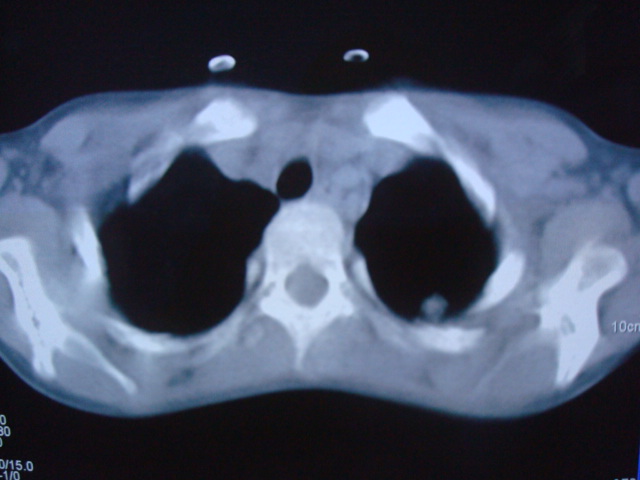

标题: PED0869:男,10岁,肺内多发结节+胸水 [打印本页]

标题: PED0869:男,10岁,肺内多发结节+胸水

男,10岁,左胸痛,发热轻,血象高。后到省级权威医院治疗,病情明显好转,结果几天后公布。老机器,图像质量差,见谅。